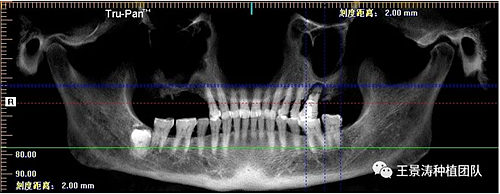

患者左側(cè)16慢性根尖周炎,17缺失。16根尖炎癥距上頜竇底較近,需內(nèi)提升,但是因為內(nèi)提升后骨質(zhì)較薄所致植入深度過深,埋入式植入。17非埋入式種植。后期效果均可。

術(shù)后一周

二期手術(shù)